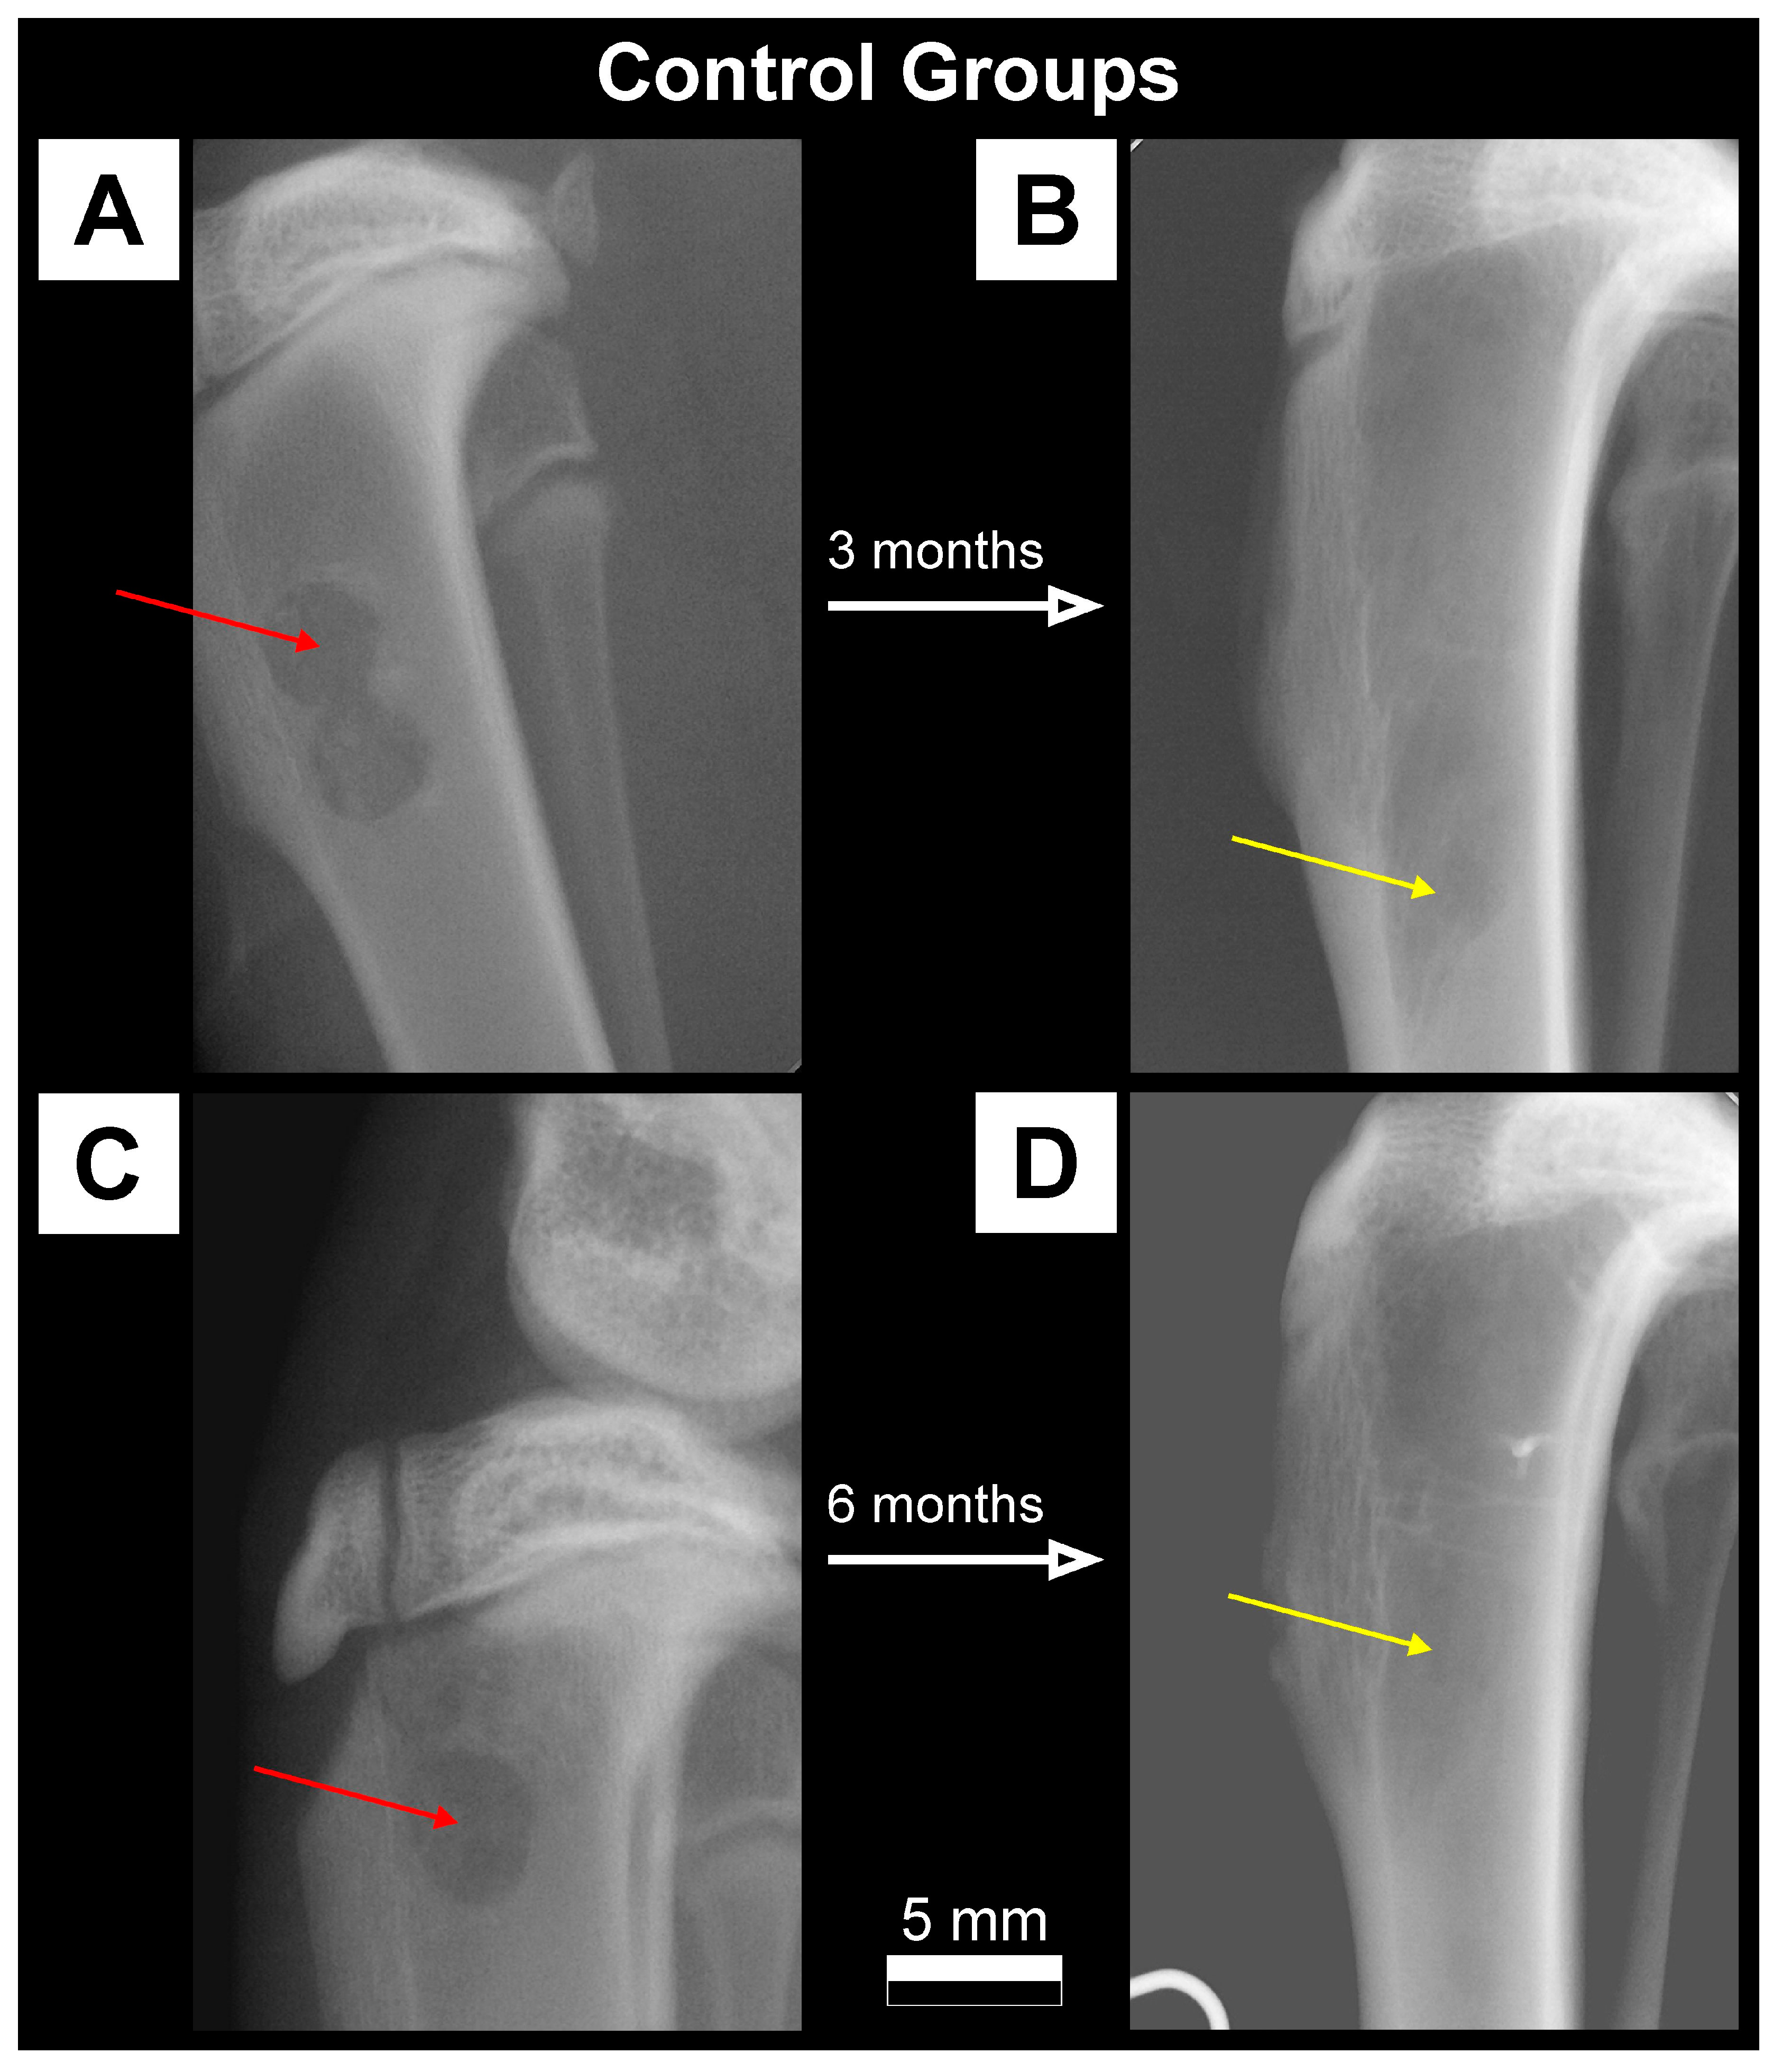

2.3.1. X-ray Imaging—Conventional Radiography

3.1. Qualitative Analysis of Bone Substitute Materials

3.2. Quantitative Analysis of Bone Substitute Materials